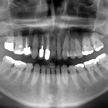

18. 術後X線写真

初診時X線パノラマ写真と比較してレントゲン上でもシンプルだと考えます。4番の近心側のPCR等は注意して、今後の定期健診に期待いたします。